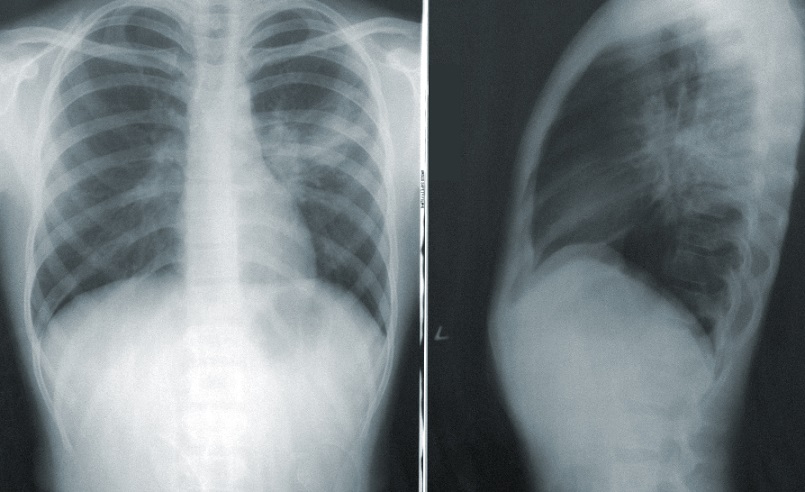

VIENA.- Las mujeres no están suficientemente representadas en los estudios médicos que se usan para el diagnóstico y tratamiento de enfermedades pulmonares, hasta el punto de que no se tiene en cuenta cómo las dosis de ciertos fármacos les afectan, según señala la Sociedad Austríaca de Neumología (ÖGP).

En dolencias como la enfermedad pulmonar obstructiva crónica (EPOC), el asma o la hipertensión pulmonar, hombres y mujeres muestran diferentes síntomas y requieren tratamientos distintos, destacó la experta.

Por ejemplo, la EPOC generalmente se asocia a hombres mayores fumadores, pero ambos sexos se ven afectados por esta enfermedad, solo que se manifiesta de forma difrerente: «Mientras los hombres tosen, las mujeres muestran cansancio y agotamiento», señaló Löffler-Ragg.

En cuanto a la hipertensión pulmonar, es más común en mujeres pero más grave en el caso de los hombres.

El asma se observa con más frecuencia en las mujeres y depende a menudo de las fases hormonales de la vida, como la pubertad, el embarazo y la menopausia, recordó la médica; «si se tuvieran en cuenta esos aspectos, se obtendría una visión más amplia de las enfermedades», añadió.